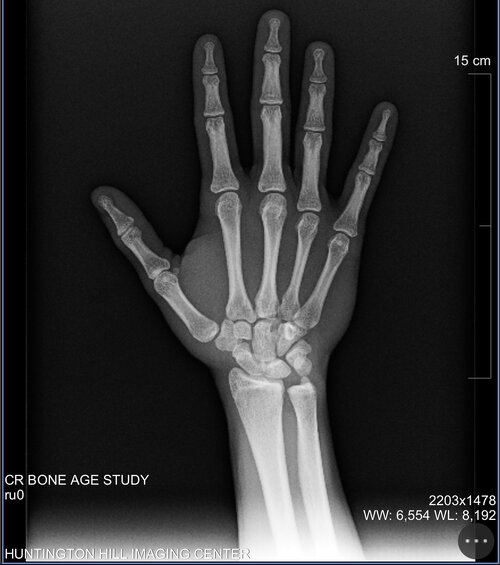

The phalangeal and metacarpal growth plates are fully fused but my distal radial growth plates are still open but nearly fused. Am I cooked or can I do anything to max my height 😭✌️